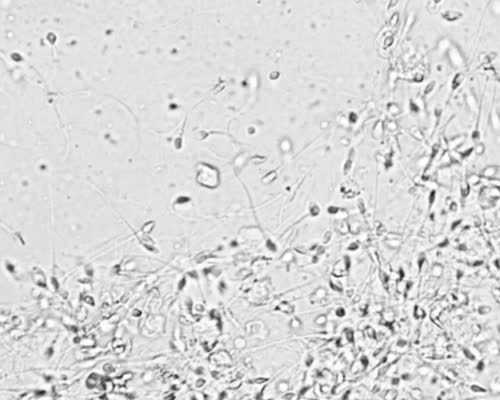

其实去做血液检测的时候,医师会抽取宝妈的外周血,即静脉血。因为外周血中含有游离的DNA片段。而要想确定宝宝的性别,只需要确定这些DNA片段中是否含有Y染色体的片段就行了。因为通常女性体内是不含有Y染色体片段的,如果检测出Y染色体片段,那么宝宝一定是男孩,反之,则为女孩。

其实,Y染色体上含有一种上世纪就被科研人员发现的被命名为"SRY"基因。这种基因能被特定的试剂染色,出现特定的颜色。所以检测人员通常会通过高速离心将染色体分离出来,然后通过染色,看看是否出现特定的颜色,如果出现,那么就含有Y染色体片段,那么宝宝就是男孩,反之,就是女孩。

香港验血查宝宝性别的技术原理:是检验胎儿游离在母亲血液中的DNA,从中分析出宝宝的性染色体,男性为XY,而女性是XX,所以在通过抽取孕妇的手臂静脉血液的情况下,来检测这其中的性染色体,胎儿在子宫中成长时,营养全部来自于母体,所以在孕妇的血液中会一部分来自于胎儿的DNA片段,这部分就是我们检测的重点!

通过DNA测序技术,来还原遗传信息,从中寻找是否存在Y染色体,在分析提取出的胎儿相关数据时如果检测到Y性染色体那么结果就是男孩子,反之就是女孩子。这种完全贴合科学依据的技术是值得依靠的,也是真是存在的,所以家长朋友是不需要任何的疑问的。我们检验的材料也仅仅对孕妇的手臂静脉血进行取样,来检查。在安全性上更是十分可靠,完全不会对宝宝和孕妈造成任何的伤害或者影响。